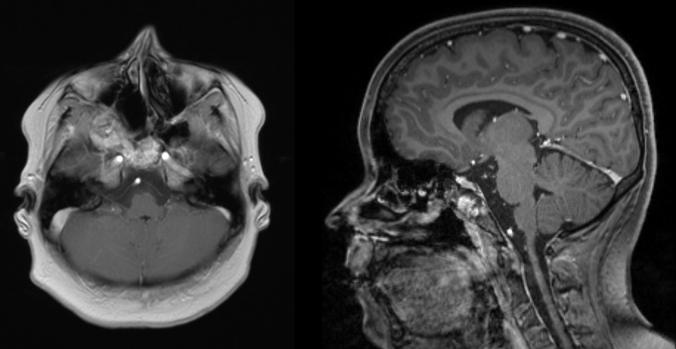

Endoscopic surgery of an extensive aneurysmatic bone cyst of the paranasal sinuses in a 12-year-old patient.

Braz J Otorhinolaryngol. 2019 Nov-Dec;85(6):803-808. doi: 10.1016/j.bjorl.2016.04.008. Epub 2016 May 6.

https://cdn.ncbi.nlm.nih.gov/pmc/blobs/dc25/9443026/37bdcf821937/gr1.jpg